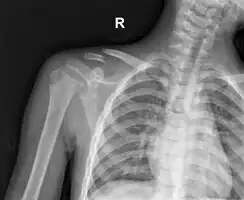

The basic method to check for a clavicle fracture is by an X-ray of the clavicle to determine the fracture type and extent of injury. In former times, X-rays were taken of both clavicle bones for comparison purposes. Due to the curved shape in a tilted plane X-rays are typically oriented with ~15° upwards facing tilt from the front. In more severe cases, a computerized tomography (CT) or magnetic resonance imaging (MRI) scan is taken. However, the standard method of diagnosis through ultrasound imaging performed in the emergency room may be equally accurate in children.[6]

Clavicle fracture